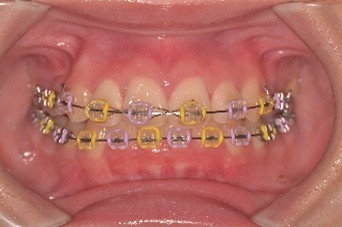

(↑ワイヤー矯正後)

ワイヤー矯正は、歯にブラケットとワイヤーをつけていきます。その後1~2か月毎に歯科医院にきてクリーニングや虫歯の有無、歯並びの状態などを確認と調整をしていきます。ある程度並んだ後、ブラケットとワイヤーを外してマウスピース矯正に移行しました。